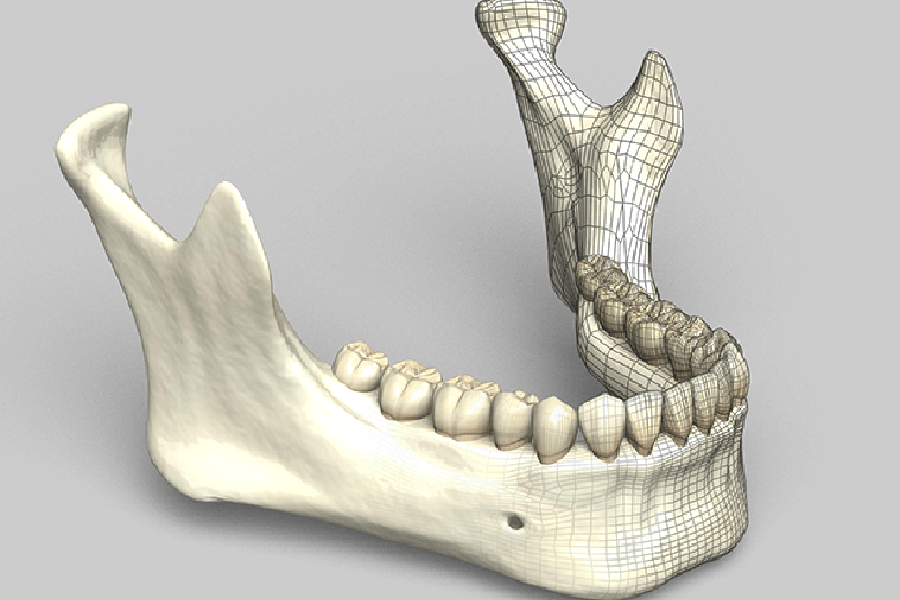

02 ミスのリスクを減らすガイドシステム

ガイドサージェリーによる

安全性の高い手術

事前に作成した3Dシミュレーションをもとに、手術中のドリルの角度や深さを誘導する「サージカルガイド」 を使用します。

これにより、術者の感覚に頼らない、ブレのない・再現性の高い手術 が可能になります。